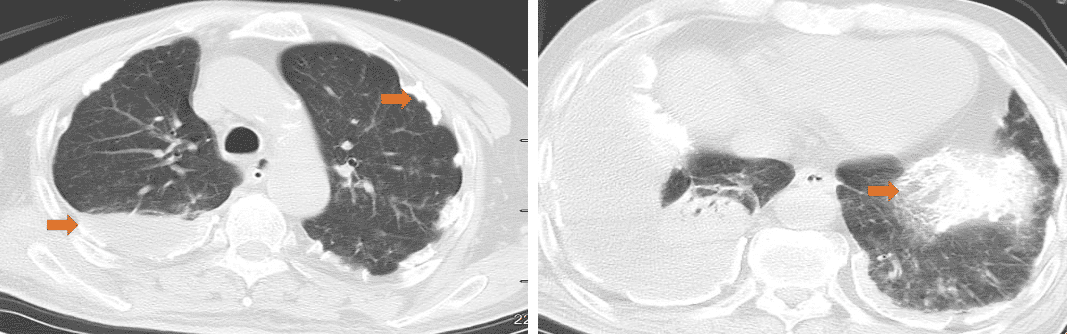

胸部CT(2025-7-30 本院):双肺见条片状高密度影,右侧胸腔内可见包裹性液体密度影。双侧胸膜增厚,部分钙化。